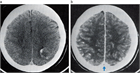

1. 脳静脈血栓症はCTやMRIにて診断を行う。特に、MRIのT2*強調画像Susceptibility-Weighted ImageSWIとMRV(magnetic resonance venography)、あるいはCTV(CT venography)でまず診断を行い、必要に応じて脳血管造影を行うことが推奨される(推奨度1)